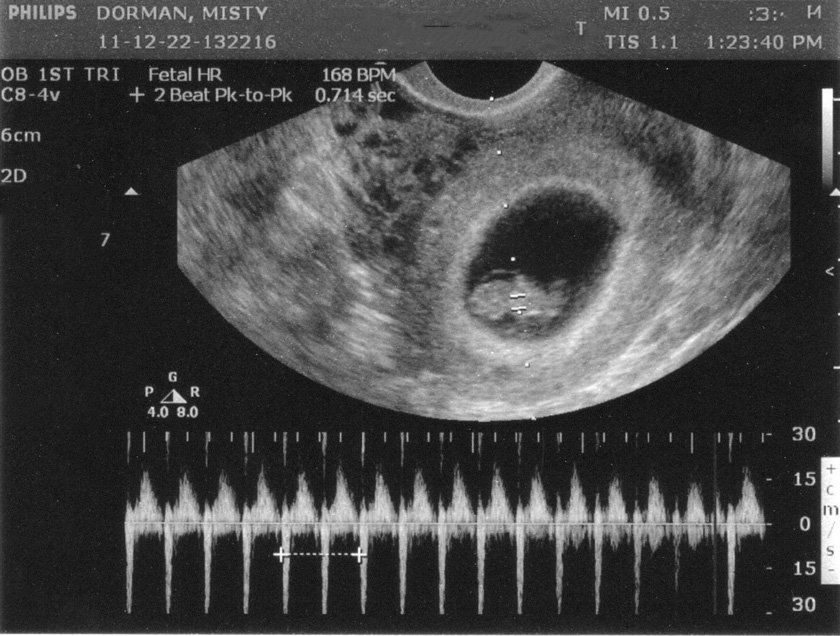

Tuần hoàn của thai nhi đi qua phổi thông qua một ống động mạch; gan cũng được bỏ qua ống thông tĩnh mạch và máu có thể đi từ tâm nhĩ phải đến tâm nhĩ trái thông qua buồng trứng. Nhịp tim thai bình thường là từ 110 đến 160 nhịp mỗi phút. Khi so sánh với người lớn, thai nhi đã giảm khả năng làm đầy thất và giảm khả năng co bóp.